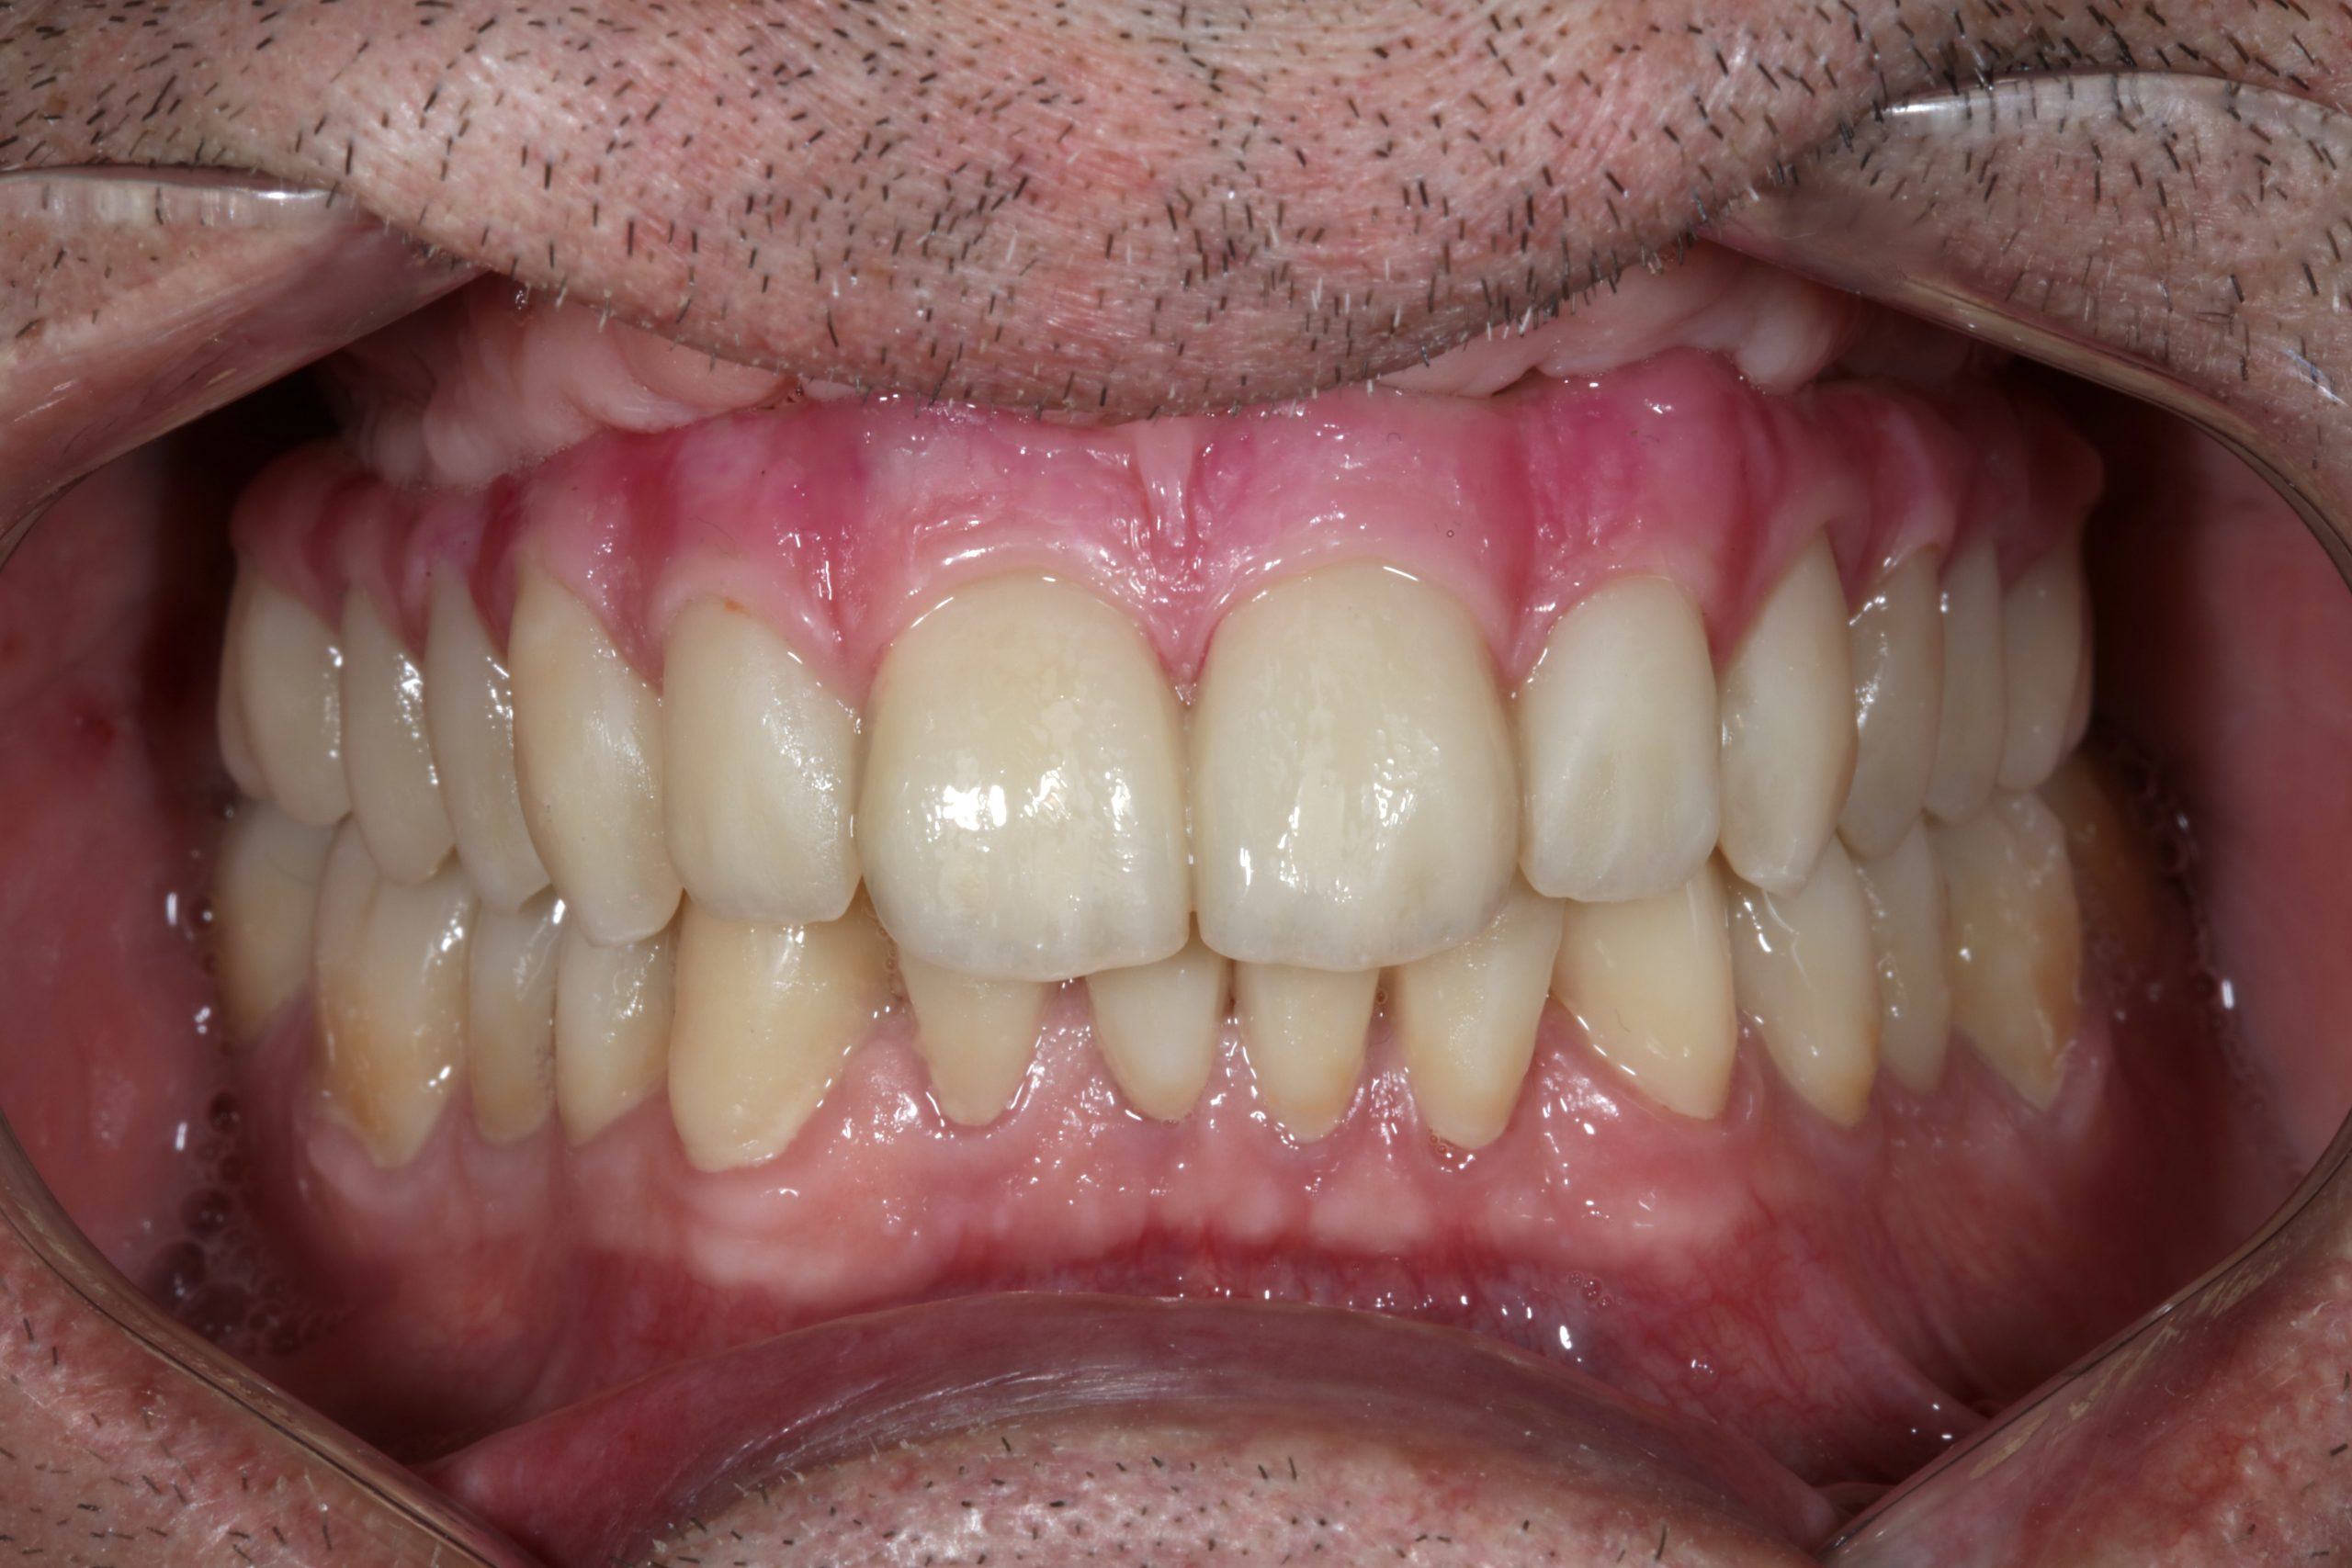

The use of CDP (Complete Digital Patient) as a basis for planning in a case of complete implant rehabilitation with a full arch in zirconia – ceramicised

Complete Digital Patient (CDP): guided surgery for complete upper and lower rehabilitation with zirconia-ceramic screw-retained implants

Complete Digital Patient (CDP): the use of guided surgery for implant restoration in total upper and lower rehabilitation with titanium bars and different types of zirconia-ceramic

Upper and lower prosthetic rehabilitation with titanium bars and translucent zirconia-ceramic structures. The CDP as an aid in communication between the entire team and the patient, who is the focus of the work.